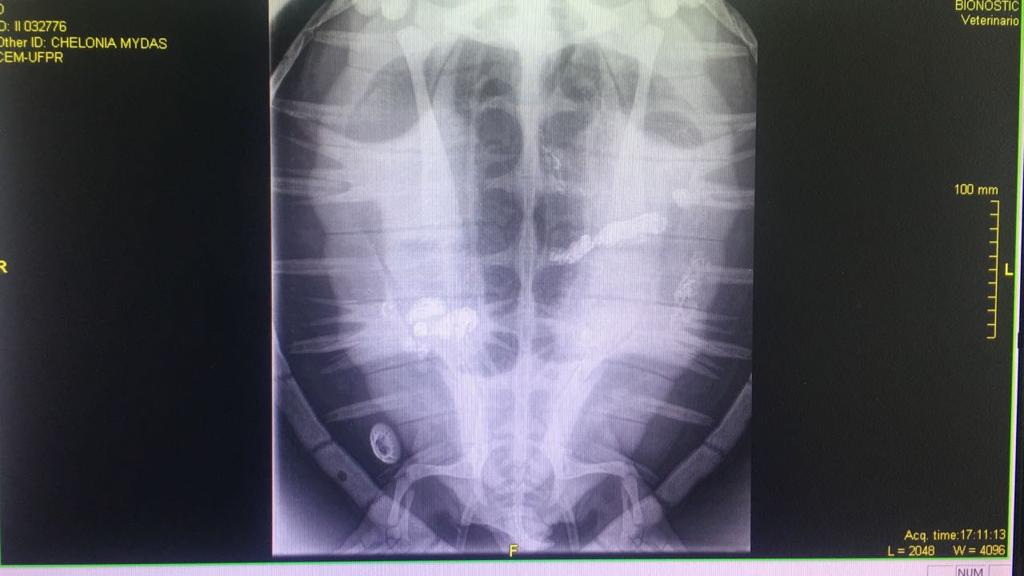

“Na tartaruga maior identificamos lixo em vários pontos do sistema digestivo. Isso cria fecalomas, que são bolos de fezes que travam todo o sistema, fazendo com que o animal não consiga comer, nem defecar”, explica Camila Domit, bióloga coordenadora do LEC, que integra o Centro de Estudos do Mar (CEM) da UFPR. De acordo com a bióloga, o lixo no sistema digestivo pode causar infecção generalizada e levar à morte do animal.

A outra tartaruga trazida a Curitiba para exames semana passada estava muito magra, com aspecto ainda mais debilitado. “Não conseguimos visualizar exatamente o lixo no sistema dessa tartaruga pequena, mas ela também está com fecalomas. Provavelmente o lixo que está nela é do tipo que não dá para ser identificado pelo raio-X, como fios de nylon, por exemplo”. O nylon é usado para fazer redes de pesca.